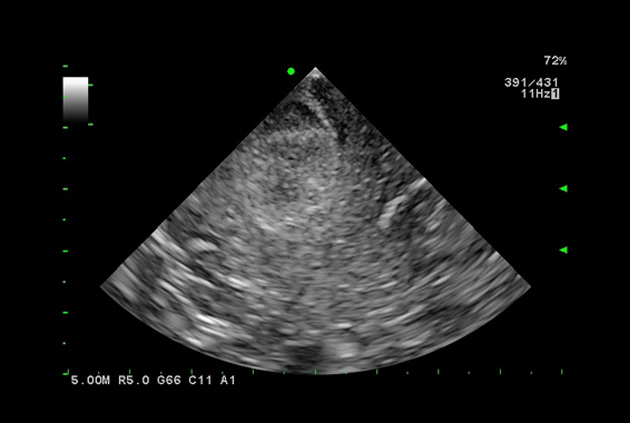

State-of-the-art digital architecture and advanced imaging features

Imaging Clearly Defined

State-of-the-art digital architecture and advanced imaging features to redefine the capabilities of surgical ultrasound.